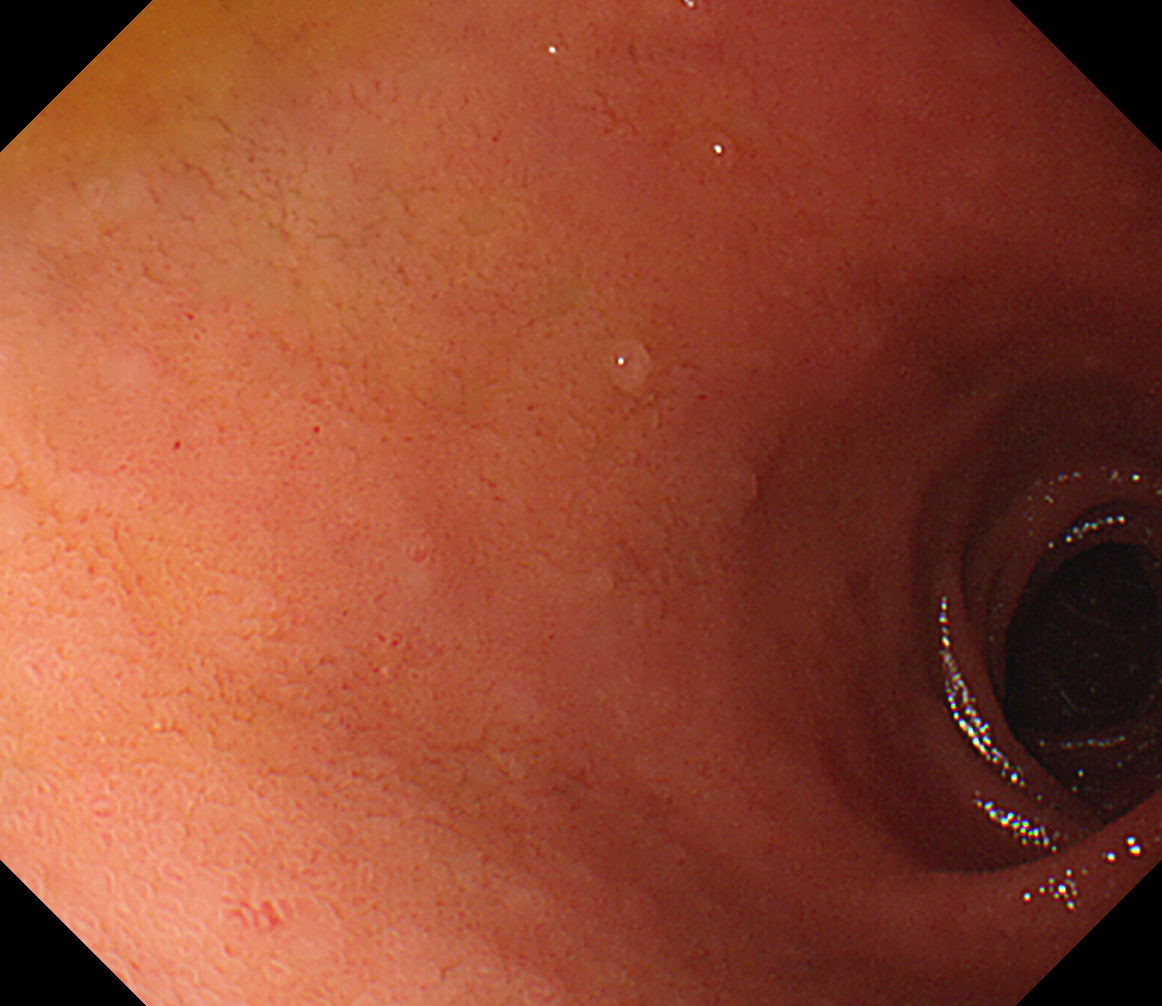

8 幽門輪 いわゆる「PーRing」 幽門輪

9 十二指腸球部前壁 十二指腸球部前壁

10 十二指腸球部後壁 この後十二指腸下降脚とVater乳頭を観察します 中部食道

11 胃角部後壁 [見下ろし]になります 中部食道

12 胃角部小弯 [J反転]見上げになります 胃角部後壁

13 胃角部前壁 再度、[見下ろし]になります 胃角部前壁